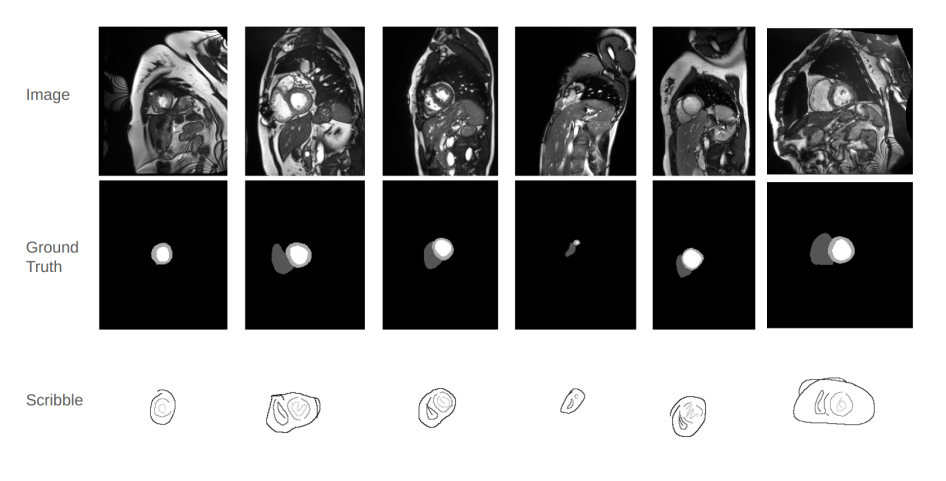

The Example Images of MRI Cardiac Scans, with the Corresponding Ground Truth, and Scribble-based Annotations.

论文提出的Weak - Mamba - UNet是一种用于基于涂鸦的医学图像分割的弱监督学习框架,结合了Mamba、CNN 和 Vision Transformer(ViT)的优势。

该方法构建了三个具有相同对称编码器 - 解码器结构的网络:基于 CNN 的 UNet 用于提取详细的局部特征,基于Swin Transformer的SwinUNet用于理解全局上下文信息,基于Visual Mamba的Mamba - UNet用于高效建模长程依赖关系。

通过使用伪标签的协作和交叉监督机制,在有限监督信号的条件下,实现三个网络之间的迭代学习和优化,最小化由基于涂鸦的部分交叉熵损失和密集信号伪标签骰子系数损失组成的总损失,以提升分割性能。